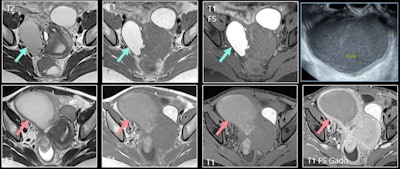

A 39-year-old woman was diagnosed with deep pelvic endometriosis. MRI showed typical endometrioma of right ovary; unilocular cyst with hypersignal greater than fat in T1-weighted image (top row, middle image), persisting in T1-weighted fat-suppressed image (top row, right image) and with shading in T2 (top row, left image). Patient presented several months later with pelvic pain, fever, and hyperleukocytosis. Increase in size, loss of shading on T2 (bottom row, left image), loss of hyperintensity on T1-weighted fat-suppressed image, and thick, enhanced wall were consistent with infected endometrioma. Ultrasound-guided drainage led to removal of 250 cc of pus (top right). All figures courtesy of Dr. Caroline Mandoul and RSNA 2020.Endometriosis is a relatively common disease, having an estimated prevalence of between 5% and 20% in women of reproductive age, and radiologists must know about the acute complications of endometriomas, the group explained in an RSNA 2020 e-poster for which they received a certificate of merit.

The sonographic appearance may be similar to an uninfected endometrioma. On MRI, there is an increase in the size of a known endometrioma, as well as a reduced typical endometriotic signal (loss of hyperintensity in T1-weighted FS imaging and loss of shading in T2). Other signs are marked restriction of diffusion with very low apparent diffusion coefficient (ADC) values, thick enhanced walls, and pelvic stranding.

"Superinfected endometriomas lose their typical endometriotic MRI signal and show marked restriction of diffusion with low ADC values," noted Mandoul and colleagues.